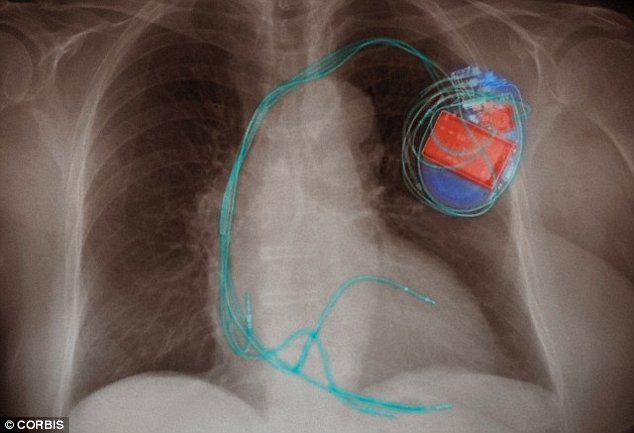

Transferring power wirelessly deep into the body of humans can revolutionize the biomedical devices. A technology is being developed in California to do all this. The technology developed has the potential to eliminate the use of heavy and boorish batteries whose implantation in the body requires to complicated medical surgeries. The system is already being tested on a small rabbit by making a heart pacemaker. Now the plans are to extend the project to human beings. The designed heart pacemaker device can easily be recharged by using a small card from outside the body.

The main objective of the system is to use the ultra-small biomedical device implants in the near future. The system has been named as “electroceuticals” can also be very effective in curing certain brain disorders. In the case of heart pacemaker, the most important thing is its tiny size besides ability to be charged wirelessly. Dr. Ada Poon, the inventor of the technology, at Stanford University says, “We need to make these devices as small as possible to more easily implant them deep in the body and create new ways to treat illness and alleviate pain.”